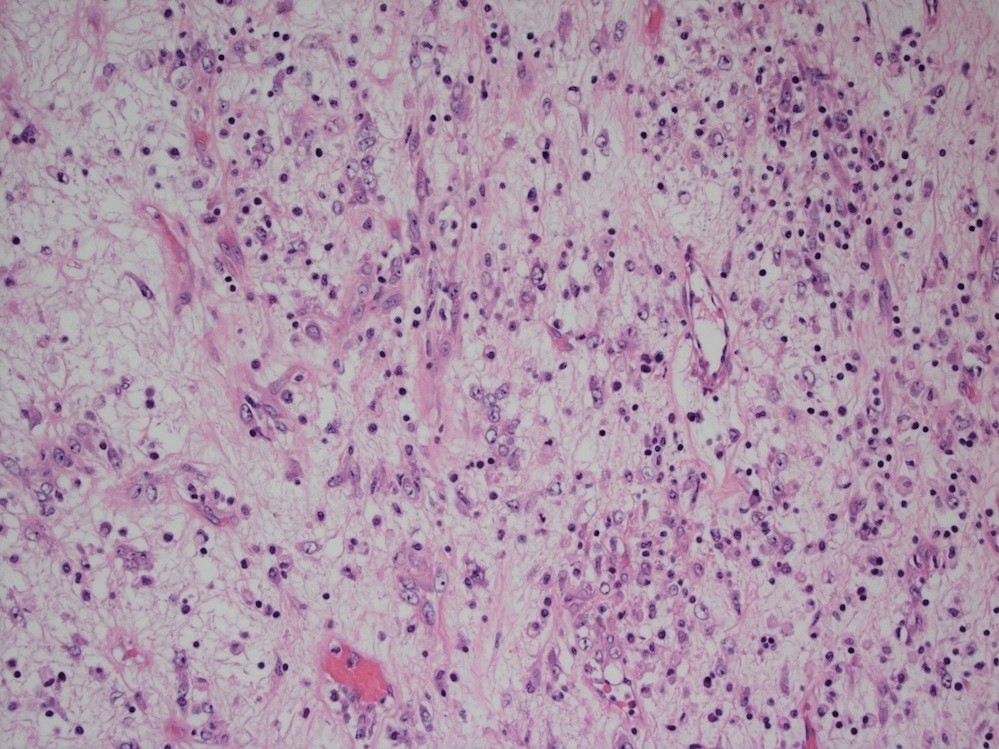

Microscopic (histologic) description

- Bland spindle cells with abundant amphophilic cytoplasm and variably prominent nucleoli

- Lymphoplasmacytic infiltrate with polyclonal plasma cells

- Background may show myxoid change or laminated / whorled fibrosis

- Epithelioid inflammatory myofibroblastic sarcoma: similar, except cells are more epithelioid, with large nucleoli

Contributed by Raul S. Gonzalez, M.D.

Contributed by Michael Feely, D.O.

A young male patient presents with abdominal pain. Imaging reveals a large mesenteric mass, which is resected. An image of the tumor’s histology is seen above. Immunohistochemistry shows ALK1 staining of the nuclear membranes. What molecular abnormality is present in this tumor?